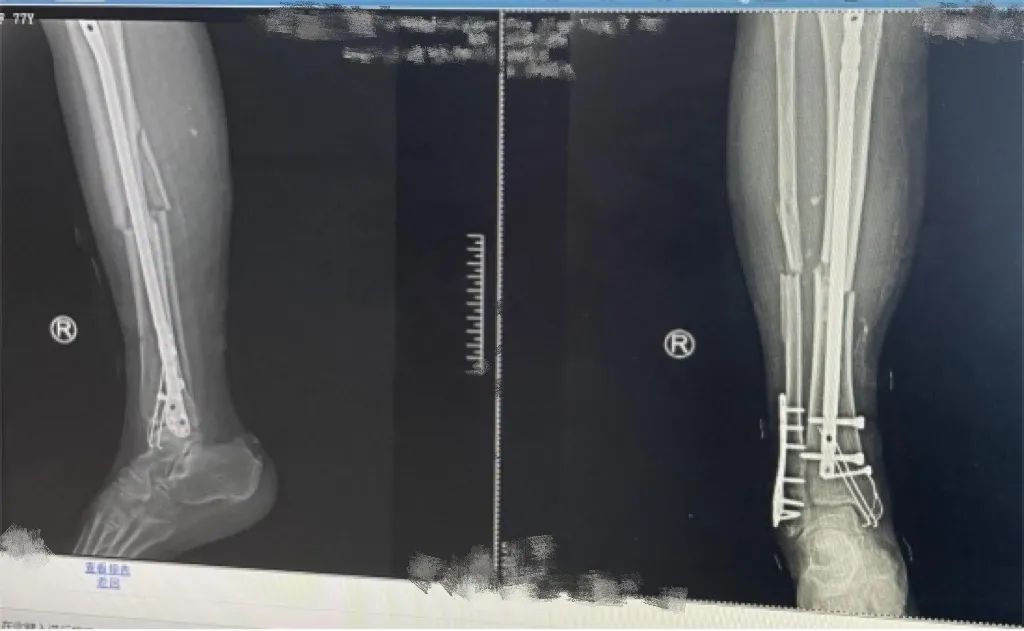

大年三十,刘女士(化名)和往年一样,前去山中上坟扫墓。扫墓的地点位于山中,山路崎岖陡峭,上山下山都要扶着旁边树木才走得稳一点。祭奠完祖先,眼看往回走了一半,刘女士在半山腰的时候却不小心踩了空,右脚崴下去,一屁股蹲在石头上。当时刘女士只觉得右边腿脚疼痛难忍,龇牙咧嘴地坐在地上起不来,好在家属比较冷静,他让刘女士先不要动,然后喊来几个帮忙的人,吃力地将刘女士抬到附近卫生院检查。拍片提示:胫腓骨及踝关节骨折,胫腓骨为开放性骨折,为进一步诊治,建议刘女士转去市直医院。

(术前)

患者入院后,骨科主任尚锦梁高度重视,立即查看伤情,紧急处理伤口,将患者外露伤口、皮肤缺损区域进行清创,并打钢针进行牵引,因患者患有糖尿病,胃口不太好,食欲不佳,住院期间想尽办法改善她的饮食习惯,期间给予两次输血。经过一周的牵引、换药,患者伤口逐渐消肿且未被感染。尚主任结合患者病史、体征及检查结果决定为其进行手术,最终经过精细分工,默契配合,医护人员们顺利地完成了手术,术后患者安返病房。

(术后)